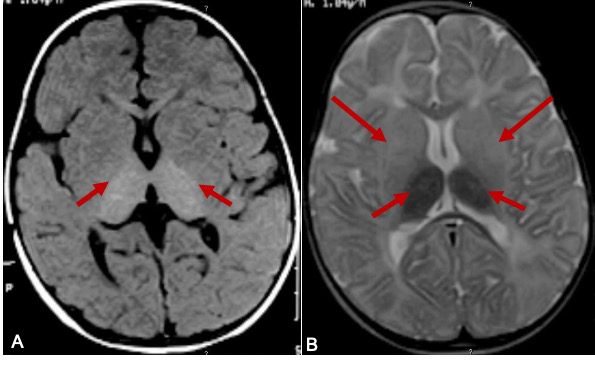

Canavan disease is a member of the family of genetic disorders known as the Leukodystrophies. The leukodystrophies are a group of disorders that affect the myelin sheath. The myelin sheath is the fatty coating that covers the nerve fibers in the brain and spinal cord insulating and protecting it. The myelin sheath is a substance that is intricate and composed of at least 10 different chemicals. Each one of the leukodystrophies affects only one of these chemicals. In canavan disease the enzyme affected is known as aspartoaclyase. aspartoacylase is responsible for breaking down a substance known as N-acetyl-L-aspartic acid or NAA. Although the exact function of NAA isn’t clear it is primarily found in the nerve cells of the brain and is believed to play a role in myelin production. Recent studies have indicated that when NAA is not properly broken down it causes a chemical imbalance that interferes with the formation of myelin during the development of the nervous system. As the NAA builds up it causes increased destruction of the existing myelin coating the nerve cells. When the nerve cells do not have the myelin sheath to coat and protect them they malfunction and die causing damage to the brain and nervous system.

As a rule the symptoms of canavan disease tend to manifest early in infancy. However, it can vary from child to child. Infants born with canavan disease usually appear to develop normally during the first few months of their life. Then around 3 to 5 months of age they begin to have difficulty with development. They begin to demonstrate delays in developing motor skill like controlling movement of their head, turning over and being able to sit without support. Babies with canavan disease usually have a larger head size, poor muscle tone and an abnormal posture as well as mental disabilities. Many also have seizures and sleep disturbances as well as feeding and swallowing problems.